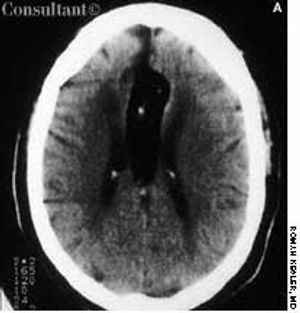

A 57-year-old man complained of a severe headache of sudden onset while he was lifting heavy boxes. Within minutes, he collapsed and became unconscious. On arrival at the emergency department, the patient was deeply comatose. His pupils were 7 mm, fixed, and unreactive to light; brainstem reflexes were absent, and he was unresponsive to noxious stimulation. His blood pressure was 210/120 mm Hg; he had no known history of hypertension.